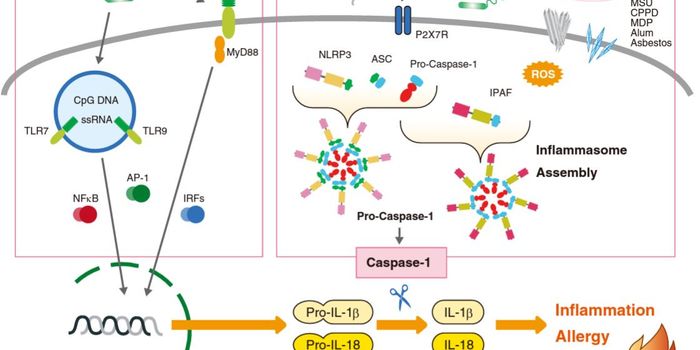

NOV 07, 2023ImmunologyPublished by Beata Boczkowska, Ph.D. Interleukin-18 (IL-18) is an effective pro-inflammatory cytokine for the host defen ...